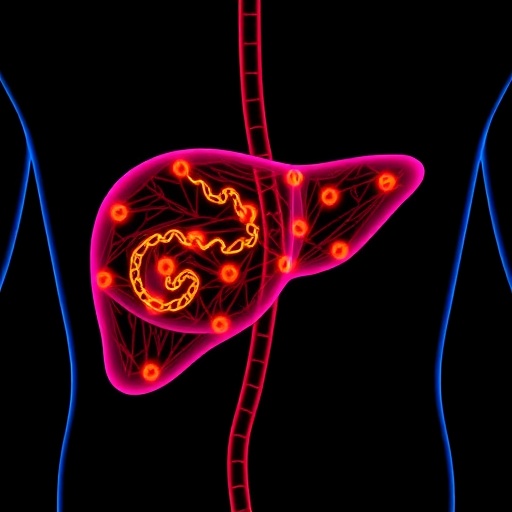

In a groundbreaking study conducted at the Salk Institute, scientists have unveiled a pivotal molecular mechanism governing the liver’s circadian rhythm for fat secretion, shedding new light on the intricate interplay between metabolism and the body’s internal clock. This research reveals that Fibroblast Growth Factor 1 (FGF1), a protein previously recognized for its roles in cellular growth and repair, operates as a crucial circadian timekeeper, orchestrating the daily export of fat from the liver into the bloodstream. This discovery not only advances our understanding of fundamental liver physiology but also carries profound implications for tackling metabolic disorders such as Metabolic Dysfunction-Associated Steatotic Liver Disease (MASLD).

The liver’s role as an energy supplier is well-documented—it packages triglycerides and other fats and releases them into circulation, thus fueling vital organs including the heart and muscles during periods of increased activity. Intriguingly, this process does not occur haphazardly but follows a tightly regulated 24-hour cycle, synchronizing with the body’s circadian rhythms. Until now, however, the molecular signals linking the circadian clock to this lipid trafficking remained elusive. The Salk Institute’s latest investigations identify FGF1 as the missing molecular link that sets the timing of hepatic fat secretion, coordinating energy delivery precisely when peripheral tissues demand it most.

To directly investigate the functional significance of FGF1 in liver metabolism, the researchers engineered mouse models lacking FGF1 expression exclusively in hepatic tissues. The abrogation of this molecular clockwork resulted in disrupted circadian fat secretion, causing pathological fat accumulation within the liver. This pathological state predisposed animals to accelerated progression of MASLD, mirroring disease pathogenesis observed in human metabolic syndrome. Conversely, therapeutic reintroduction of FGF1 in mice with established MASLD arrested further disease advancement, offering a tantalizing prospect for novel intervention strategies that target the underlying temporal orchestration of liver fat metabolism.

The implications of this study are far-reaching. By dissecting the molecular basis of hepatic lipid rhythmicity, the work paves the way for fundamentally new approaches to prevent and treat disorders characterized by dysregulated lipid metabolism. Such conditions include not only MASLD but also related pathological states like steatohepatitis and metabolic syndrome, which collectively represent a growing global health burden. Targeted modulation of FGF1 signaling or its downstream pathways could offer precise therapeutic windows tailored to the body’s natural biological rhythms, enhancing efficacy and minimizing side effects.